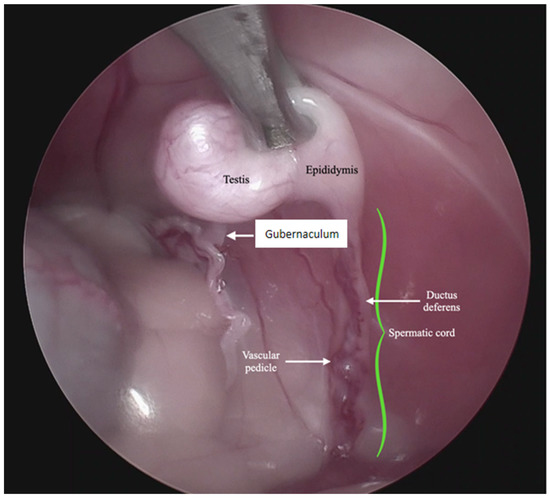

In 13 cases, the coagulation and cutting of the vascular pedicle, the spermatic cord, and the gubernaculum were performed with advanced electrothermal bipolar energy devices (eight with the Laparoscopic Tissue Sealer G2-ENSEAL® Ethicon-Johnson & Johnson (New York, NY, USA) and five with LigaSureTM Covidien-Medtronic (Dublin, Ireland), https://www.jnjmedtech.com/global, https://www.medtronic.com/covidien/en-us/index.html accessed on 27 October 2022) (Figure 3). In five cases, this procedure was made with a Harmonic scalpel device (Figure 4 and Supplementary Video S1) (Harmonic ACE® +Shears and Gen11 generator Ethicon-Johnson & Johnson), and in one case, with the use of a monopolar energy hook.

Figure 4.

Technique with three access ports. View of the maneuvers of the testis support with a grasping of forceps and coagulation and cutting of the vascular pedicle, spermatic cord, and gubernaculum, performed with a harmonic scalpel device. (See Supplementary Video S1 in Supplementary Materials.)

The following supporting information can be downloaded at: https://www.mdpi.com/article/10.3390/ani13010181/s1, Video S1: Technique with three access ports. View of the manoeuvres of the testis support with a grasping forceps and coagulation and cutting of the vascular pedicle, spermatic cord, and gubernaculum, performed with a harmonic scalpel device.